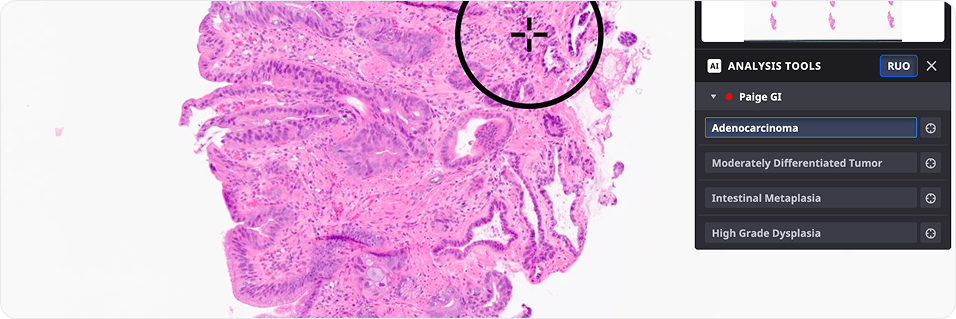

Identifying MSI-High in Prostate Cancer Using AI-Powered Digital Pathology. p-MSI predicts potential MSI-H status in people with prostate cancer, helping clinicians identify specimens more likely to benefit from MSI testing.

Development and validation of a deep learning-based microsatellite instability predictor from prostate cancer whole-slide images

An AI model effectively predicts MSI-H status from H&E-stained prostate cancer slides, potentially streamlining immunotherapy eligibility assessment and Lynch syndrome testing

Deep Learning Identifies Microsatellite Instability in H&E Whole Slide Images from Prostate, Esophageal, and Gastric Cancers and Generalizes across Cancer Types